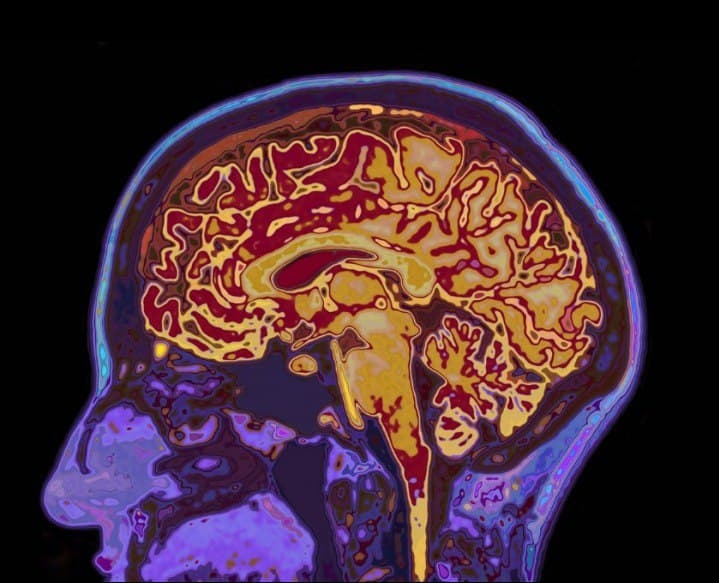

कोरोना वायरस सिर्फ श्वसन तंत्र को ही नहीं प्रभावित करता है बल्कि केंद्रीय तंत्रिका पर भी दुष्प्रभाव डालता है। इससे अलग-अलग न्यूरोलाजिकल लक्षण जैसे- स्वाद पहचानने की शाक्ति में कमी आना, सिरदर्द, थकान और चक्कर आदि दिखने लगता है।

हाल ही हुए एक अध्ययन में यह बात सामने आई है। पाया गया है कि कैसे वायरस संक्रमित की नाक से दिमाग में प्रवेश कर सकता है। इससे यह पता लगाना संभव हो सकेगा कि कोविड-19 बीमारी के दौरान मरीजों में न्यूरोलॉजिकल लक्षण क्यों उभर रहे हैं और उसका कैसे इलाज किया जा सकता है। जर्मनी की यूनिवर्सिटी का यह अध्ययन नेचर न्यूरोसाइंस पत्रिका में प्रकाशित हुआ है।

अध्ययन में 71 वर्ष औसत आयु की 11 महिलाएं व 22 पुरुष शामिल थे। अनुसंधानकर्ताओं का कहना है कि संक्रमितों के मस्तिष्क व श्वसन नली में सार्स-सीओवी-2 आरएनए (वायरस का जेनेटिक मेटेरियल) व प्रोटीन के तत्व मिले हैं। इस तरह के मामले देश में भी देखने में आ रहे हैं।